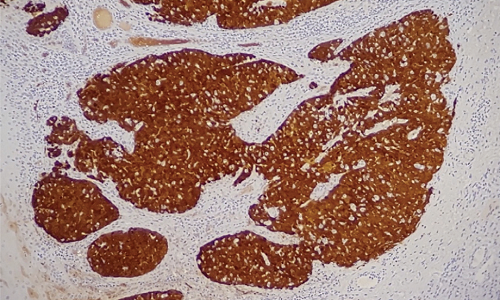

The Utility of Immunohistochemistry in Diagnosing Tubulocystic Renal Cell Carcinoma with Papillary Morphology

Allison Kaye Pagarigan, Erland Del Rosario

39-45

PDF